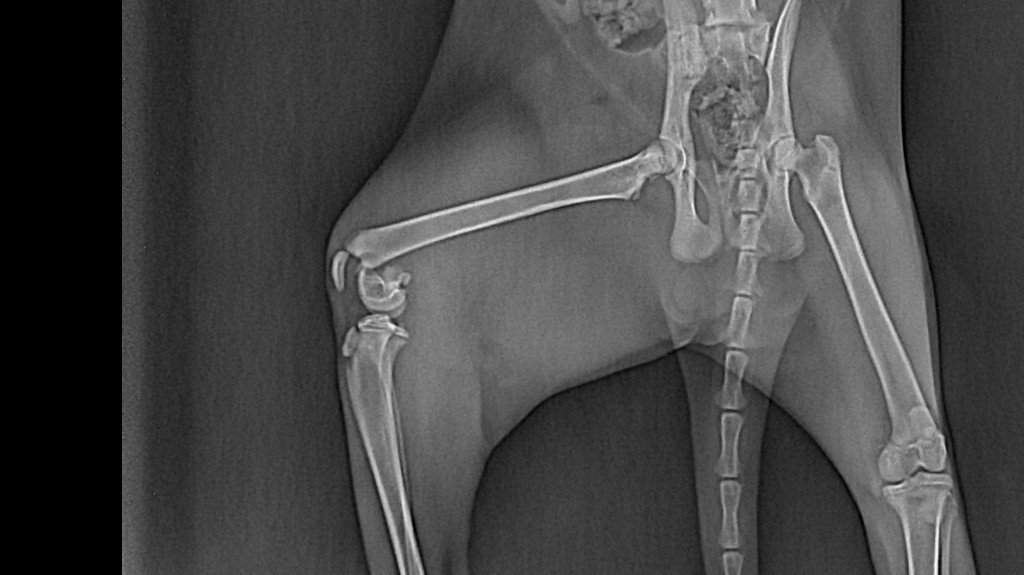

Moja kochana kotka LILI ma dopiero 6 mc a już tyle za nią.2 dni temu (10.11)zdażył się nieszczęśliwy wypadek i doznała urazu tzn konkretnie ma pęknięte lewą kość udową a prawe mocno potłuczone. Na dzień dzisiejszy od dwóch dni jest w klinice przy ul Stewczyka 11. W Lubelskim Centrum Małych Zwierząt. Lili potrzebuję operacji którą trzeba jak najszybciej zrobić, plan piątek (12.11) lub niedziela (14.11) .. A koszt jej to 1400zl. 10.11.2021 r. Lili trafiła do kliniki i do dnia dzisiejszego koszty badań i leków wyniósł około 500 zł.. bardzo proszę każdego kto ma możliwości i chęci pomóc o wpłacenie nawet najmniejszej kwoty, każda złotówka się liczy. Wiem że dla jednego to może i nieracjonalne że proszę o pieniądze na pokrycie kosztów leczenia ale niestety sytuacja mnie do tego zmusiła.. sama też nie jestem w dobrym stanie zdrowia i nie ukrywam że nie jest mi łatwo.. A ta kotka jest takim lekarstwem by choć trochę się trzymać na nogach. ( WIEM ŻE DUŻO OSÓB MOŻE NAWET NIE WIERZY, A DRUGICH TYLE TO WOGOLE NIE INTERESUJE)

Moja kochana kotka LILI ma dopiero 6 mc a już tyle za nią.2 dni temu (10.11)zdażył się nieszczęśliwy wypadek i doznała urazu tzn konkretnie ma pęknięte lewą kość udową a prawe mocno potłuczone. Na dzień dzisiejszy od dwóch dni jest w klinice przy ul Stewczyka 11. W Lubelskim Centrum Małych Zwierząt. Lili potrzebuję operacji którą trzeba jak najszybciej zrobić, plan piątek (12.11) lub niedziela (14.11) .. A koszt jej to 1400zl. 10.11.2021 r. Lili trafiła do kliniki i do dnia dzisiejszego koszty badań i leków wyniósł około 500 zł.. bardzo proszę każdego kto ma możliwości i chęci pomóc o wpłacenie nawet najmniejszej kwoty, każda złotówka się liczy. Wiem że dla jednego to może i nieracjonalne że proszę o pieniądze na pokrycie kosztów leczenia ale niestety sytuacja mnie do tego zmusiła.. sama też nie jestem w dobrym stanie zdrowia i nie ukrywam że nie jest mi łatwo.. A ta kotka jest takim lekarstwem by choć trochę się trzymać na nogach. ( WIEM ŻE DUŻO OSÓB MOŻE NAWET NIE WIERZY, A DRUGICH TYLE TO WOGOLE NIE INTERESUJE)